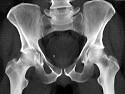

问题 男,46岁,双髋部疼痛,实验室检查血钙升高,尿本周蛋白(+),结合图像,最可能的诊断是?(?)

选项 A.骨髓瘤 B.骨质疏松症 C.骨转移瘤 D.骨囊肿 E.动脉瘤样骨囊肿

答案 A